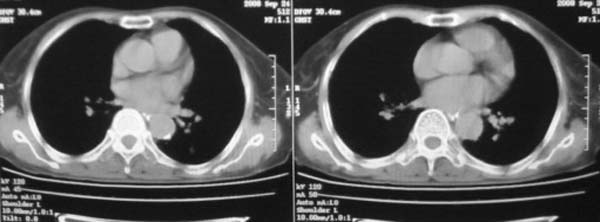

女,78岁,声嘶月余,否认有既往病史,有粉尘接触史10年。

颈部见多枚淋巴结肿大,考虑尘肺继发结核,喉部淋巴结钙化,不除外喉部慢性淋巴结炎、喉淀粉样变及类癌等

肺癌伴纵膈、双颈部淋巴结转移;尘肺。

双上肺结节融合影,周围有纤维条索影,结合粉尘接触史,首先考虑尘肺。双侧颈部有增大淋巴结,有声嘶表现,肺癌淋巴结转移不能排除。可结合颈部淋巴结活检。

考虑肺癌伴纵膈、双颈部淋巴结转移;